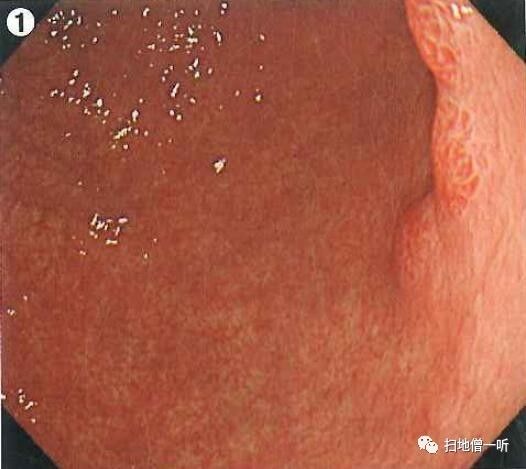

A:胃癌在图1。HP现症感染胃癌。

背景粘膜为O-1型萎缩。胃窦大弯前壁可见一中央凹陷周边隆起性病变。考虑为IIC型病变伴周围反应性隆起。

靠近观察可见凹陷面周围确有隆起。随蠕动动态观察正面观可见凹陷面呈棘状或蚕食状(黄圈部分)高度怀疑高分化腺癌。

靛胭脂染色后凹陷面界限更加清晰,周围隆起部分粘膜同周围背景粘膜,故为反应性隆起的非癌粘膜。

最终诊断:胃窦大弯前壁,O-IIc,5mm,tub1,T1a(M),UL(-)

小结:背景粘膜判断有无HP感染

反应性隆起常见于胃癌

蚕食像应高度怀疑胃癌

补充:胃体部均一的发红粘膜、糜烂性发红、大弯粘膜肿胀蛇形、粘膜不易冲洗等均提示HP感染。

对照下图为HP阴性的大弯粘膜表现。